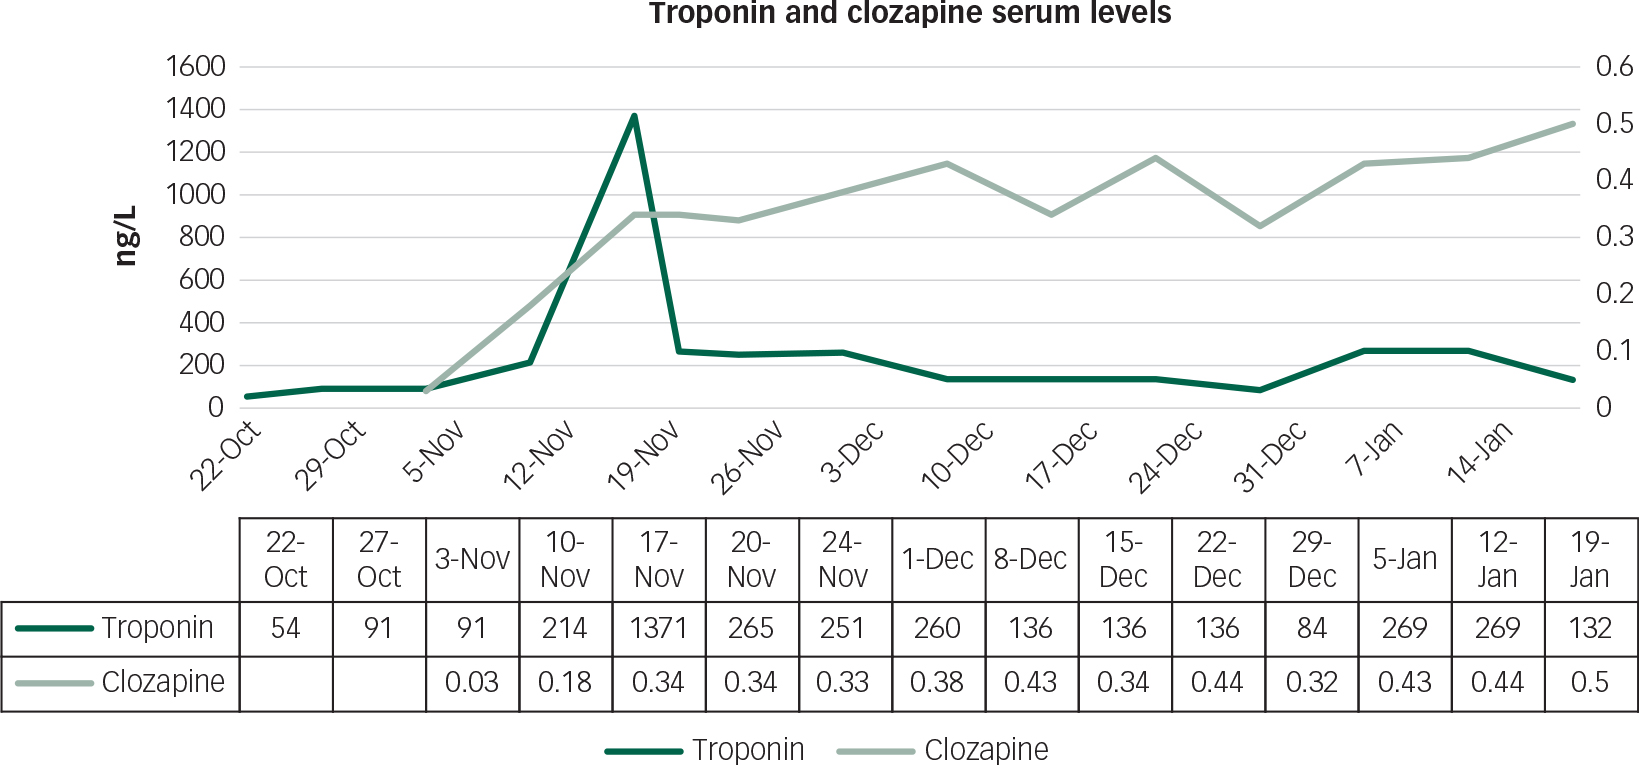

Figure 3 shows that during weeks 4–5 of clozapine up-titration, there was a spike in the troponin levels. At this point, the patient remained clinically well and was haemodynamically stable with a heart rate of 90 bpm and a blood pressure of 140/80 mmHg. Consultation with Cardiology reported that the spike represented a minor troponin leak which, in the absence of any other clinical changes, was not clinically significant. The advice was that we continue with up-titration and with continued blood testing. Figure 3 shows resolution of this event, and regular serum clozapine levels were also noted.

Fig. 3 Graph showing serum levels of both troponin and clozapine during starting and up-titration.

In our patient, a mildly increased baseline troponin was felt to relate to the increased muscle mass of the left ventricle seen in HCM. Troponin is a more specific myocardial marker than creatine kinase, and the brief elevation during the course of clozapine up-titration probably represents a very mild, self-limiting myocarditis. The underlying mechanism of cardiotoxicity by clozapine remains unclear. Several different mechanisms have been proposed, and it is likely that a combination of these is causative in susceptible individuals. It remains to be determined whether the pathophysiological processes at play in HCM, itself a condition with a wide genotypic and phenotypic presentation, pose a greater short- and long-term risk for those concurrently treated with clozapine.